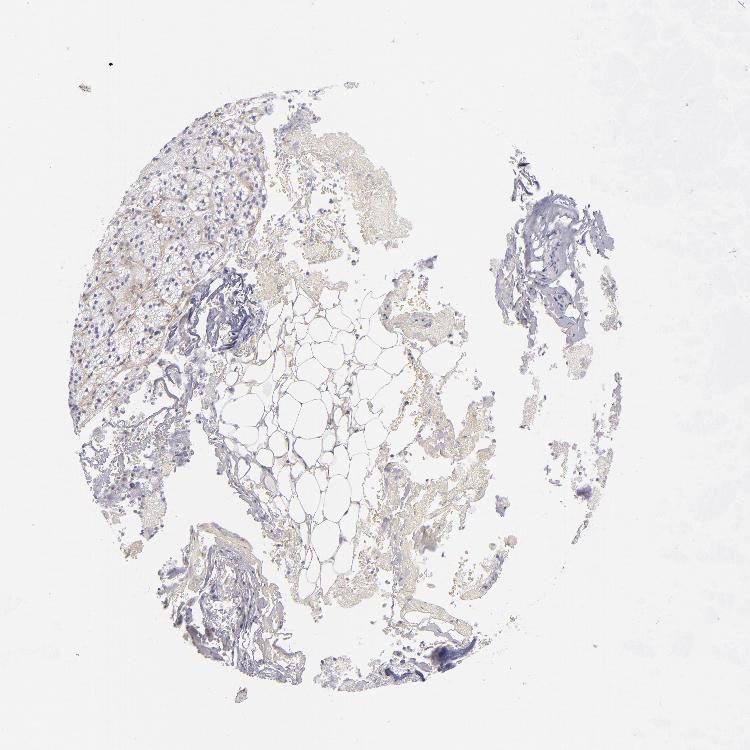

ADRENAL GLAND - Antibody stainingi

Antibody staining in the annotated cell types in the current human tissue is reported as not detected, low, medium, or high, based on conventional immunohistochemistry profiling in selected tissues. This score is based on the combination of the staining intensity and fraction of stained cells.

Each image is clickable and will lead to virtual microscopy that enables deeper exploration of all samples and also displays staining intensity scores, fraction scores and subcellular localization as well as patient and tissue information for each sample.

Antibody HPA007234Antibody CAB002507

Glandular cells Not detectedNot detected